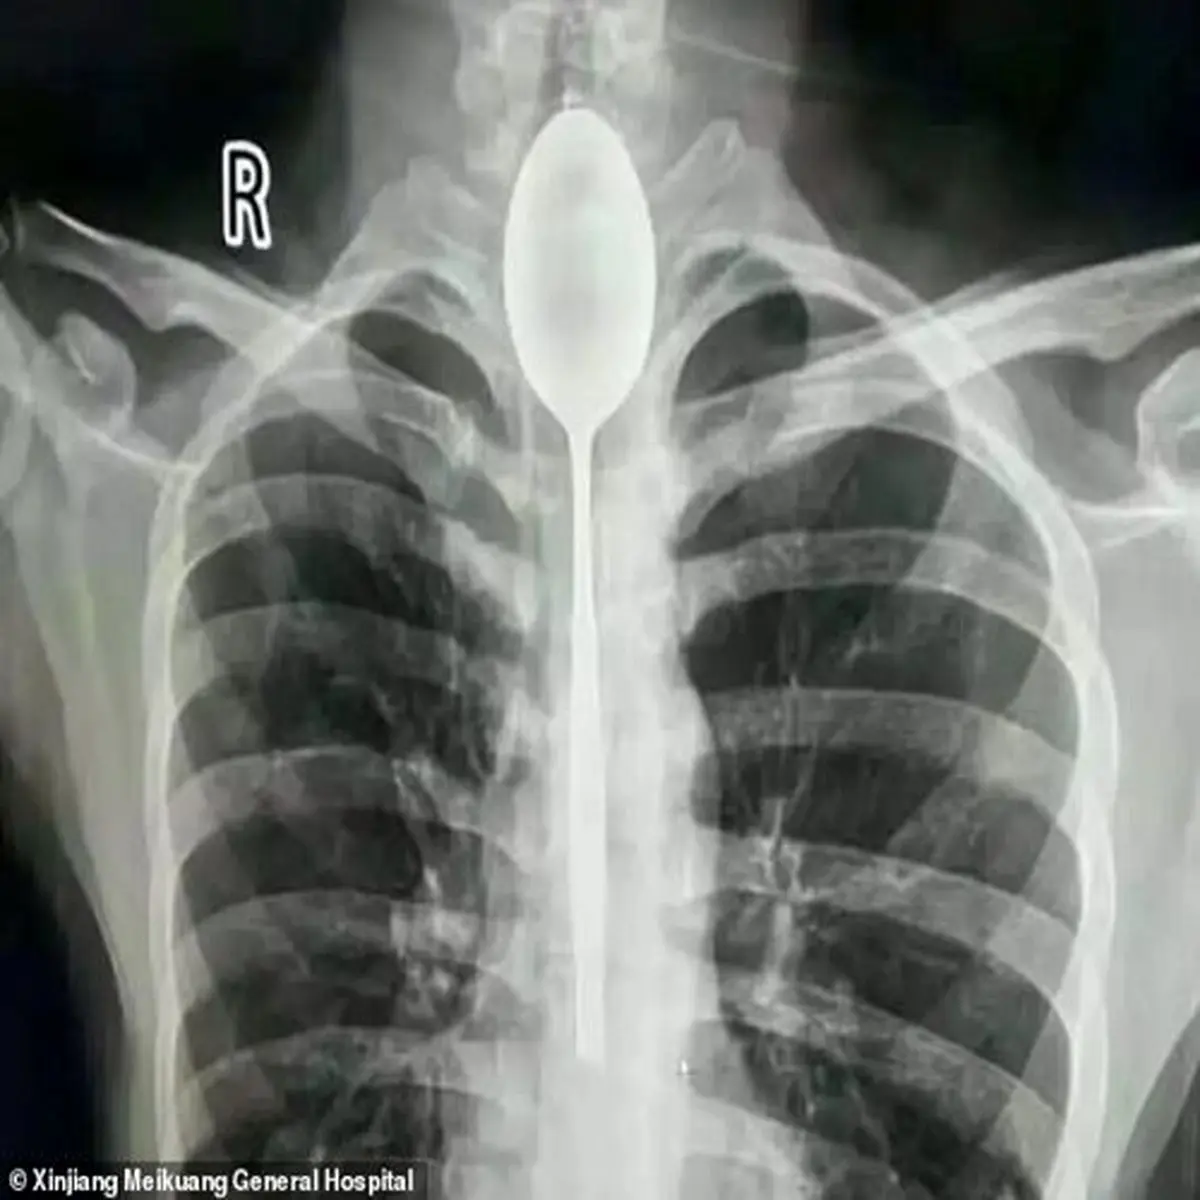

بعد از یکسال جوان چینی به دلیل درد شکم و تنگی نفس به پزشک مراجعه کرد. پزشکان بعد از مشاهده عکس رادیولوژی شوکه شدند. اما بیمار تعجب نکرد، چون به یاد داشت که یکسال پیش قاشقی را قورت داده بود؛ در این یکسال او هیچ مشکلی نداشت.

پزشکان تصمیم گرفتند تا بدون عمل جراحی و باز کردن شکم قاشق را از دهان بیمار بیرون بکشند و تنها او را بیهوش کنند. به نظر پزشکان قاشق تنها به مری آسیب زده است و به زودی جراحت آن بهبود خواهد یافت.